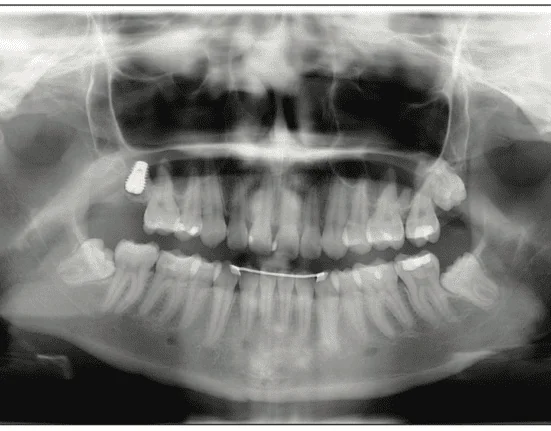

An ASA I, 20-year-old girl with a congenitally missing upper right back molar (No. 2) had pain around wisdom tooth No. 1. During the examination, it was discovered that she had an opposing second molar No. 31, and it was slightly supra-erupted due to missing tooth No. 2. The patient expressed concerns with wanting to remove wisdom tooth No. 1 due to pain resulting from pericoronitis (Figure 9).

All treatment options were presented, including the extraction of the wisdom tooth and no treatment due to possible further complications. The patient wanted another molar in the back for better chewing and to prevent supra-eruption of the lower second molar. After discussing with the patient, we devised a plan to extract tooth No. 1 and to place an implant with a sinus lift for tooth No. 2 to increase chewing efficiency and improve overall self-confidence. The sinus was pneumatized, and the residual bone height was approximately 4 mm.